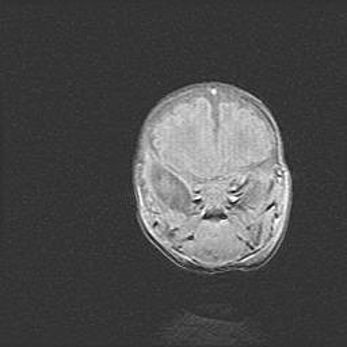

Наружная гидроцефалия с возможной атрофией височных областей.

Возраст: 28 дней

Вес: 3670 г

Пол: мужской

Окружность головы: 38 см

Срок гестации: 40 недель

Гидроцефалия головного мозга у новорожденных – это заболевание, которое характеризуется скоплением избыточного количества спинномозговой жидкости в желудочковой системе головного мозга в результате затруднения её перемещения от места выработки к месту поглощения в кровеносную систему или вследствие нарушения абсорбции. При открытой наружной форме гидроцефалии у новорожденных расширяются и переполняются субарахноидные пространства.

При нормотензивных  формах,  которые,  как  правило,  являются  следствием  перенесенных ишемических  повреждений  паренхимы  мозга,  возможно  сочетание микроцефалии  с нормотензивной гидроцефалией. В основе данных изменений лежит атрофия больших полушарий с преимущественной  локализацией  в  лобно-височных  областях.